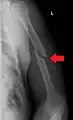

Midshaft humerus fracture with callus formation

Middle fractures are usually caused by either physical trauma or falls. Physical trauma to the humerus shaft tends to produce transverse fractures whereas falls tend to produce spiral fractures. Metastatic breast cancer may also cause fractures in the humerus shaft.[12] Long spiral fractures of the shaft that are present in children may indicate physical abuse.[5]

Fractures of the humerus shaft are most often uncomplicated, closed fractures that require nothing more than pain medicine and wearing a cast or sling. For midshaft fractures up to 12 weeks may be required for healing.[17]